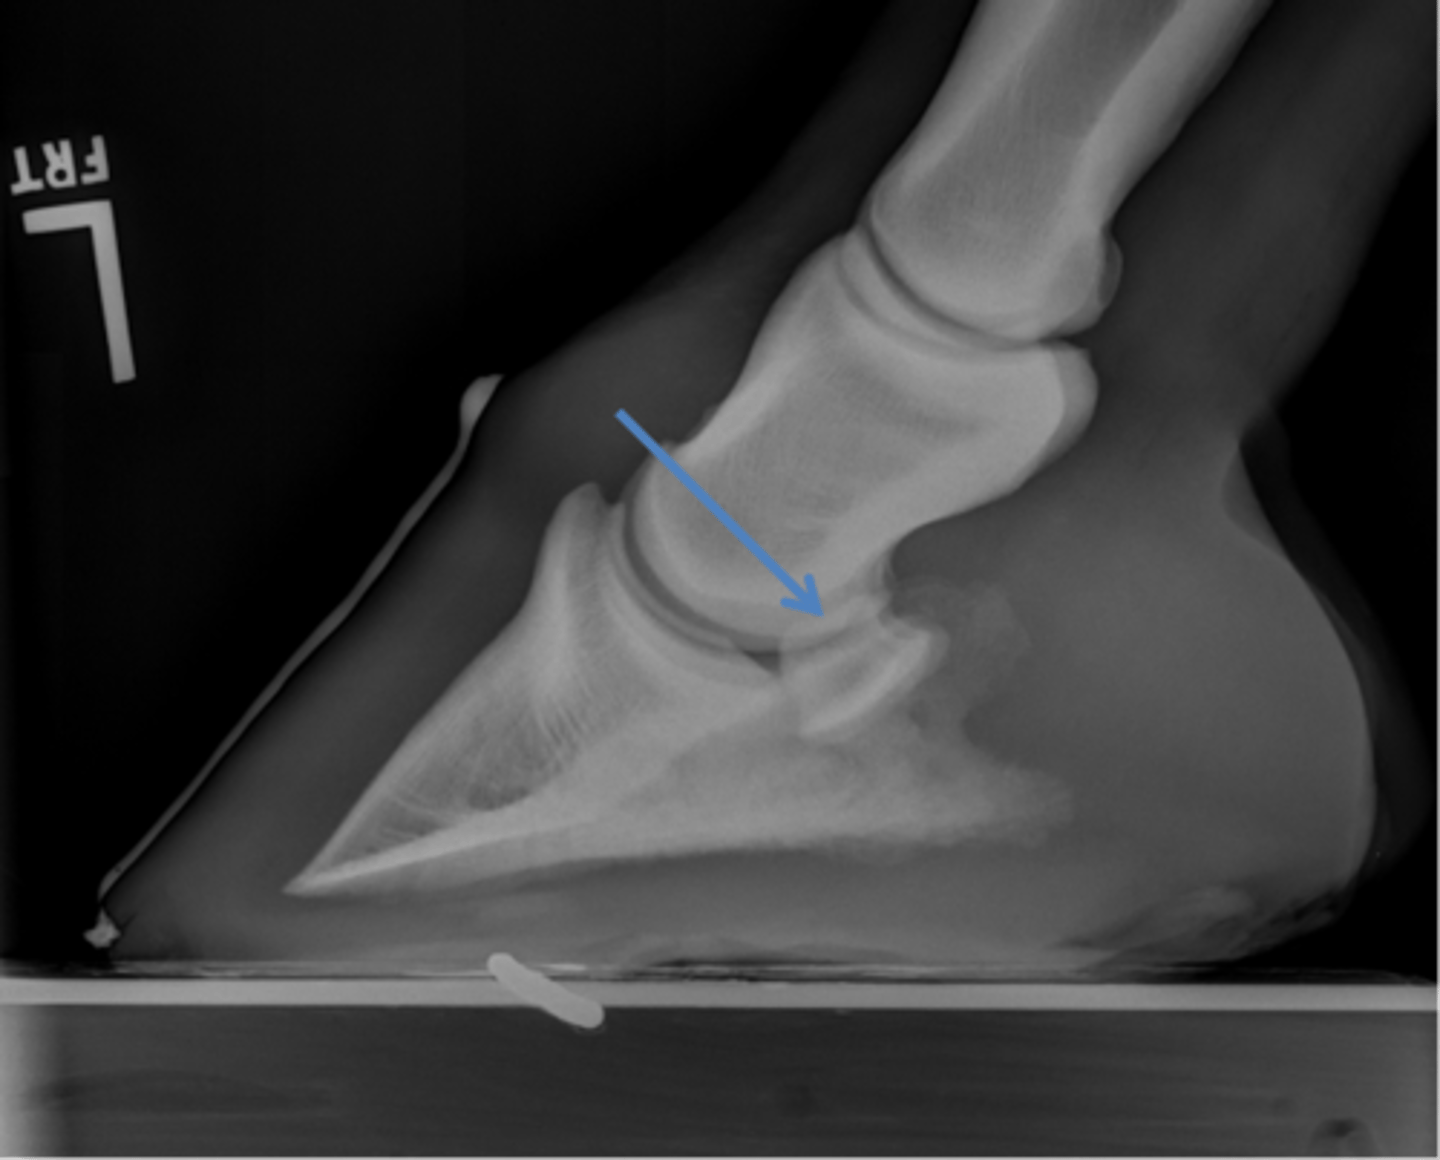

Coffin bone (P3)

Palmar process of P3

Extensor process of P3

Navicular bone

Coffin joint

Proximal interphalageal joint (pastern joint)

Short pastern (P2)

Upright pedal or high coronary

What view is this?